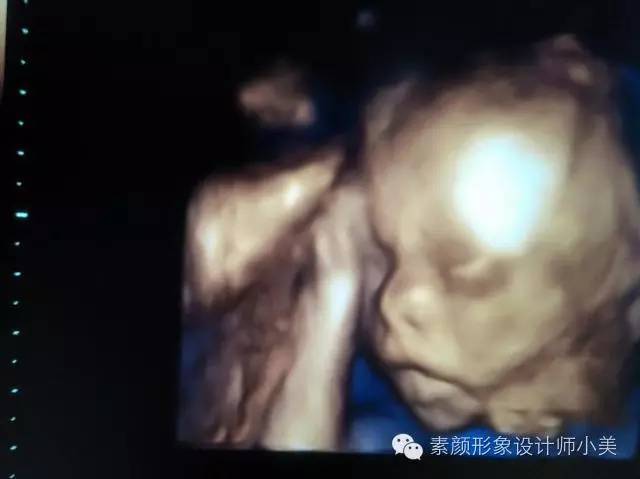

本周,胎儿的皮下脂肪已较前大为增加,皱纹减少了,身体圆润,他现在的样子已经和出生时很接近了。大多数宝宝的胎位应该已经是头位了,即头在下,臀部在上。并且宝宝的头可能在今后的6周里下沉至骨盆并开始压入子宫颈。这个姿势不仅为出生作准备,还可以使血流至他正在发育的脑部。

你知道吗?不仅仅是宝宝在为出生作准备,你的身体也在为迎接分娩作而准备呢!虽然由于身体的长大,宝宝的活动受到限制,但通过B超,妈妈已能分辨出宝宝的小膝盖、小脚和胳膊肘了。同时准妈妈也会注意到一些有节奏的轻微的碰撞,那是宝宝在打嗝呢。此时准妈妈可能会有胎膜早破的情况发生,尤其是睡觉时。